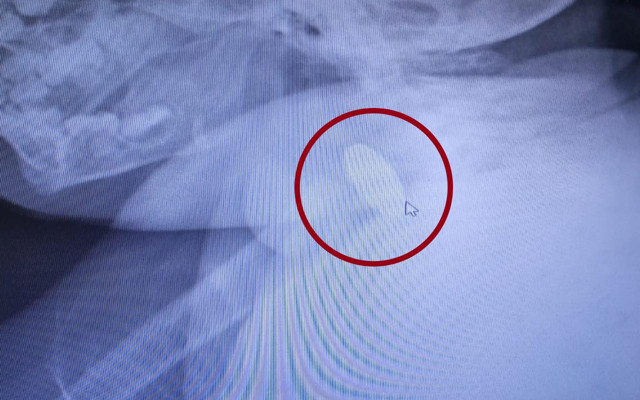

Abone olEreğli'de evde oynarken madeni para yutan 1 yaşındaki D.D.Ç., ailesi tarafından özel hastaneye kaldırıldı. Doktorların müdahalede bulunduğu D.D.Ç.'nin çekilen röntgeninde 25 kuruşluk madeni para sindirim sistemi girişinde tespit edildi. Yapılan muayenede madeni paranın bebeğin yemek borusuna zarar vermediği anlaşıldı. Doktorların müdahalesi sırasında D.D.Ç., kusması sonucu madeni para kendiliğinden çıktı. Sağlık durumu iyi olan D.D.Ç., taburcu edildi.